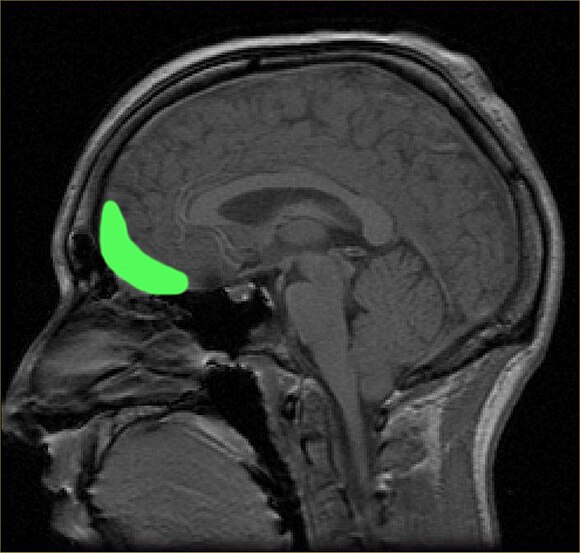

Lipton and his team have now developed a novel method that detects damage in the outermost wrinkles of the brain – a tricky spot to study using diffusion magnetic resonance imaging (dMRI).

This layer is called the cortical gray matter–white matter interface (GWI), and until recently, not much was known about it.

Those who said they took more headers showed significant changes in the GWI at the front of their brains – a spot consistent with the trajectory of a soccer ball during a header.

The authors suspect that this injury site reflects a contrecoup force – a sort of bruise to the brain that occurs on the opposite side of the skull.

OrbitofrontalThe orbitofrontal cortex, where GWI changes were observed. (Paul Wicks/Wikimedia Commons/Public Domain)

Injuries to the GWI may have gone undetected or underestimated in other imaging studies, which is possibly why there are conflicting results on the neurological impact of soccer headers.